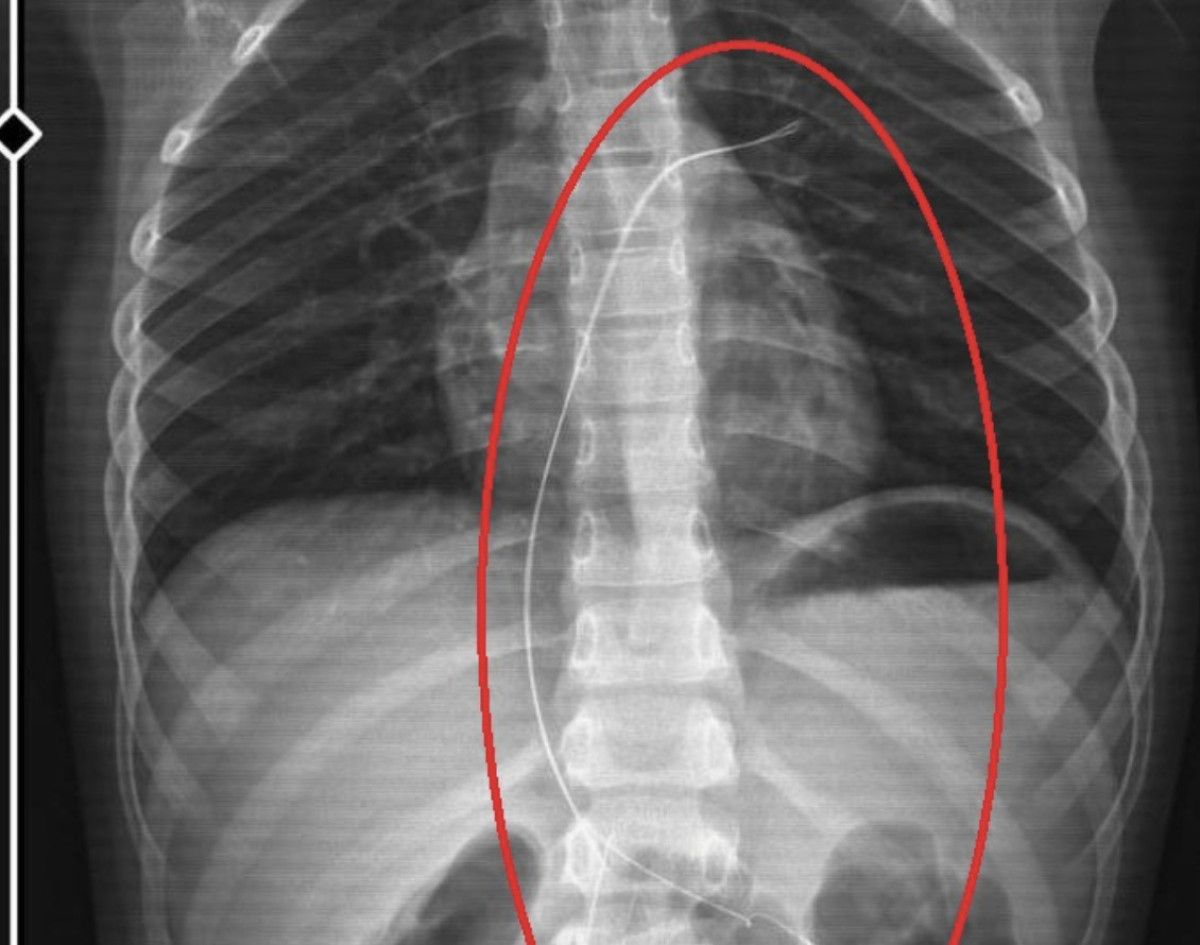

Burada çekilen röntgen ve MR’da Aram’ın vücudunda kateter unutulduğu görüldü.

Bunu takarken büyük bir ihmalkarlık yapılarak vücudunda unutuldu. Mayıs ayında müvekkilim çok öksürdüğü için Şırnak Devlet Hastanesi’ne kaldırıldı. Burada yapılan tetkiklerde kateterin unutulduğu tespit edildi.

Bu kateterin vücutta yol aldığı tespit edildi. İlk giriş yeri ve çıkarıldığı yer arasında çok fark var ve kalp kapakçığı ile ciğerlerine zarar verdiği tespit edildi.

Röntgeni ve MR’ı çekildi. Tuhaf bir şey olduğunu anladık. Doktor röntgeni gösterdi. Tel kalmıştı. Çok kötü bir şekilde. Acil doktoru film çektikten sonra bize bir tel parçasını gösterdi. Bizi bekletmeden Diyarbakır’a sevkimizi verdiler. Diyarbakır Gazi Yaşargil Eğitim ve Araştırma Hastanesi Kadın Doğum ve Çocuk Ek Binası’na gittik.